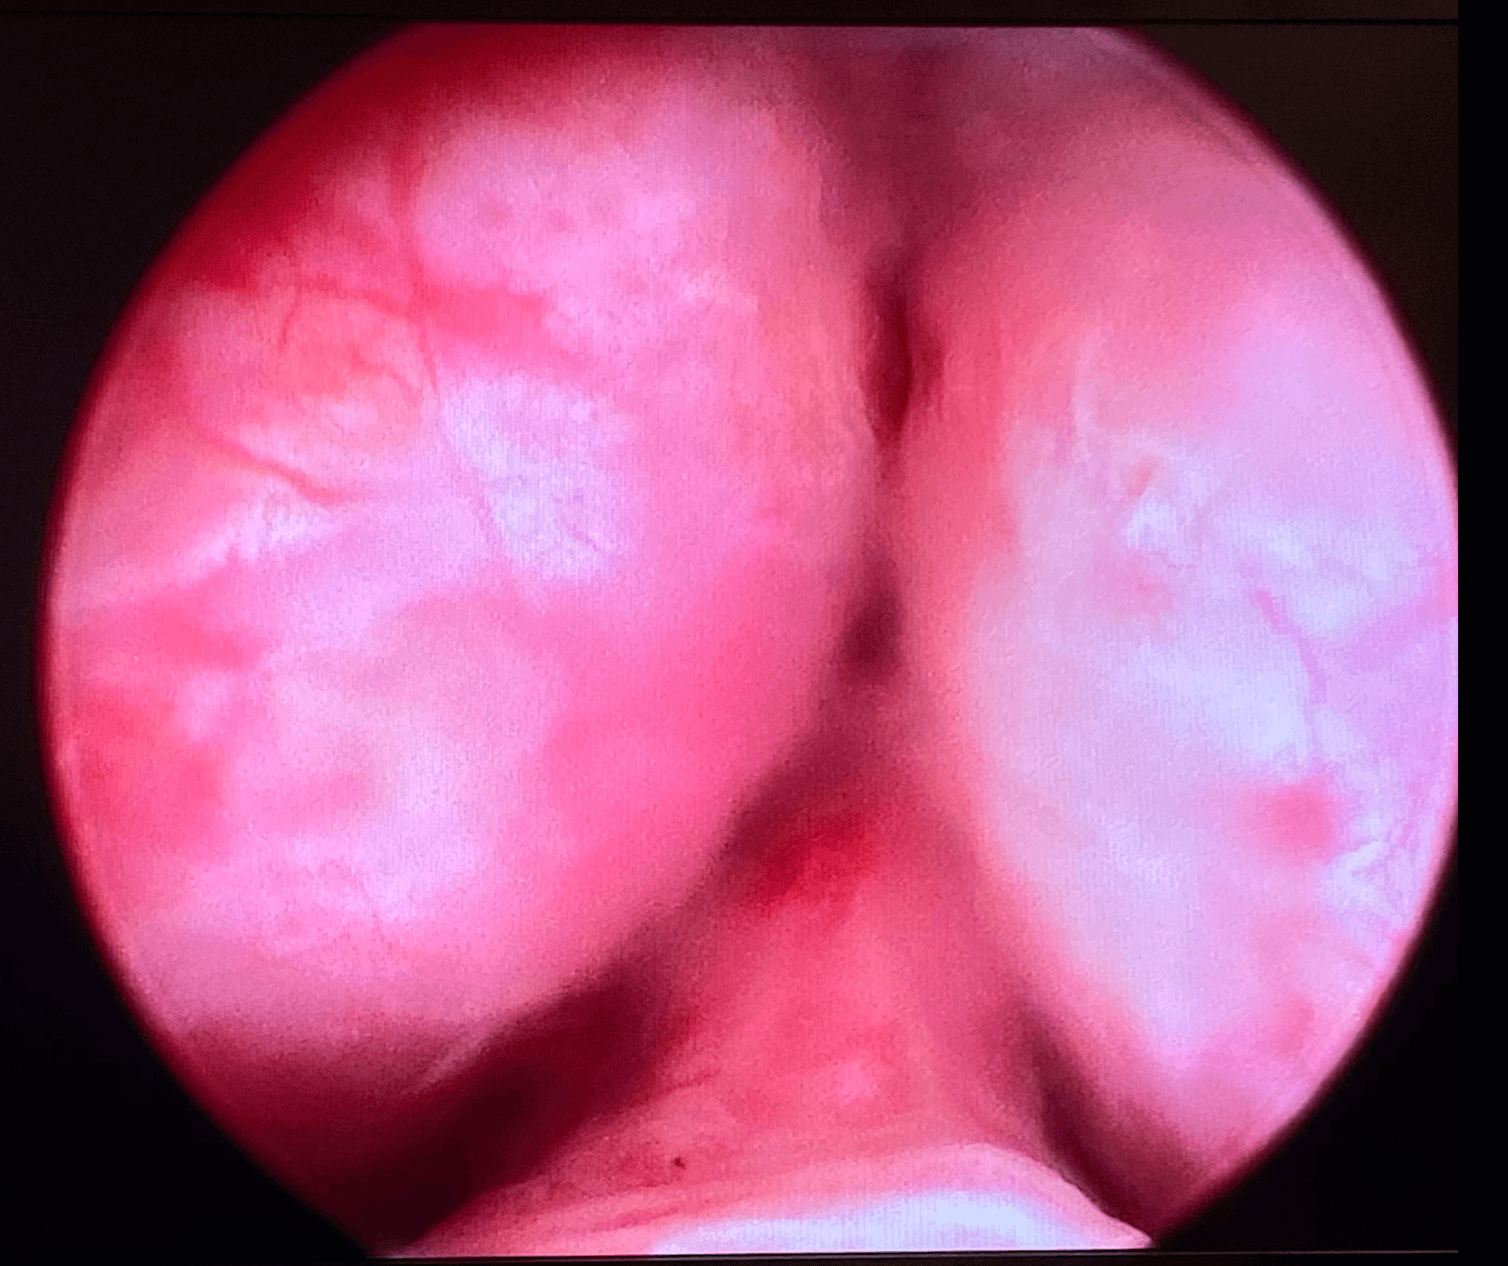

Atlanta males gets UroLift procedure

Procedure